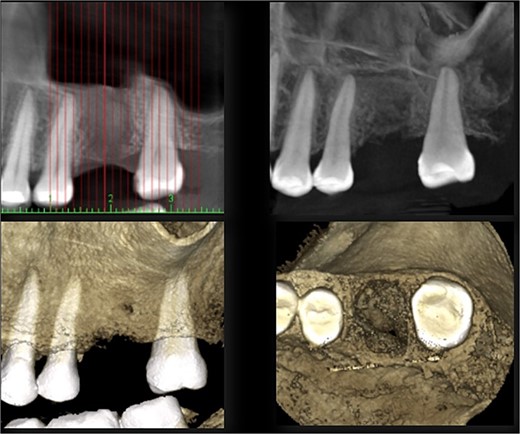

A 56-year-old female patient without any systemic diseases was referred by otolaryngology for evaluation by oral surgery due to presenting pain on the left side of the face for two weeks. The patient’s first molar presented a wide restoration (Fig. 1). This molar had undergone endodontic treatment some years ago. The CT scan showed a hyperdense left maxillary sinus almost entirely with loss of continuity of the maxillary sinus floor at the level of the left upper first molar involving the furcation zone, it is evident an oroantral communication of 7 mm (Fig. 2). The patient referred to spontaneous pain during chewing. Based on the CT scan and the clinical findings, pharmacological management was indicated with oral antihistamine 10 mg every 24 hours for 10 days, Moxifloxacin 400 mg every 24 hours, and scheduled extraction with oroantral communication closure with collagen sponge on the third day after starting the antibiotic, which will be used for a total of 10 days. The patient agreed to sign an informed consent file to make the technique to extraction and close the oroantral communication.